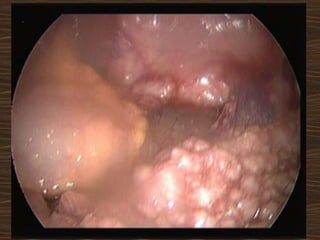

Laparoscopic hysterectomy with BSO done.

Specimen removed through

endobag

Transitional cell tumour of the ovary

Post op CT: “recurrence “ of tumour 7cm!!!!

Chemotherapy

Alive and kicking 3 years later